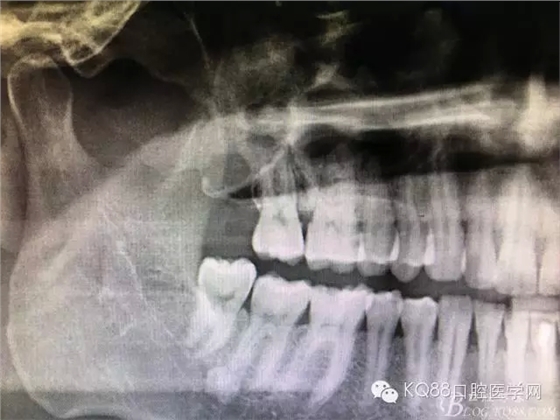

圖3.加拍CBCT影像檢查:18位于上頜竇內(nèi),并導(dǎo)致右側(cè)上頜竇粘膜炎性增生。18牙冠的合面朝向頰側(cè)。并且與17頰根緊密相鄰。

圖4.三維重建影像顯示:18牙體位于上頜竇內(nèi)。其上頜竇頰側(cè)骨壁破壞消失。左側(cè)骨壁完好無缺。

圖5. 右側(cè)三維側(cè)面觀:18位于竇腔內(nèi)。上頜竇后份的頰側(cè)骨壁完全破壞消失。